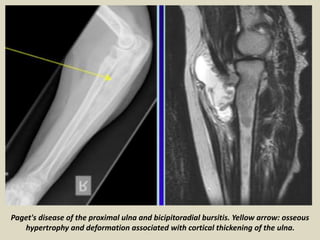

Paget's disease of the proximal ulna and bicipitoradial bursitis. Yellow arrow: osseous

hypertrophy and deformation associated with cortical thickening of the ulna.